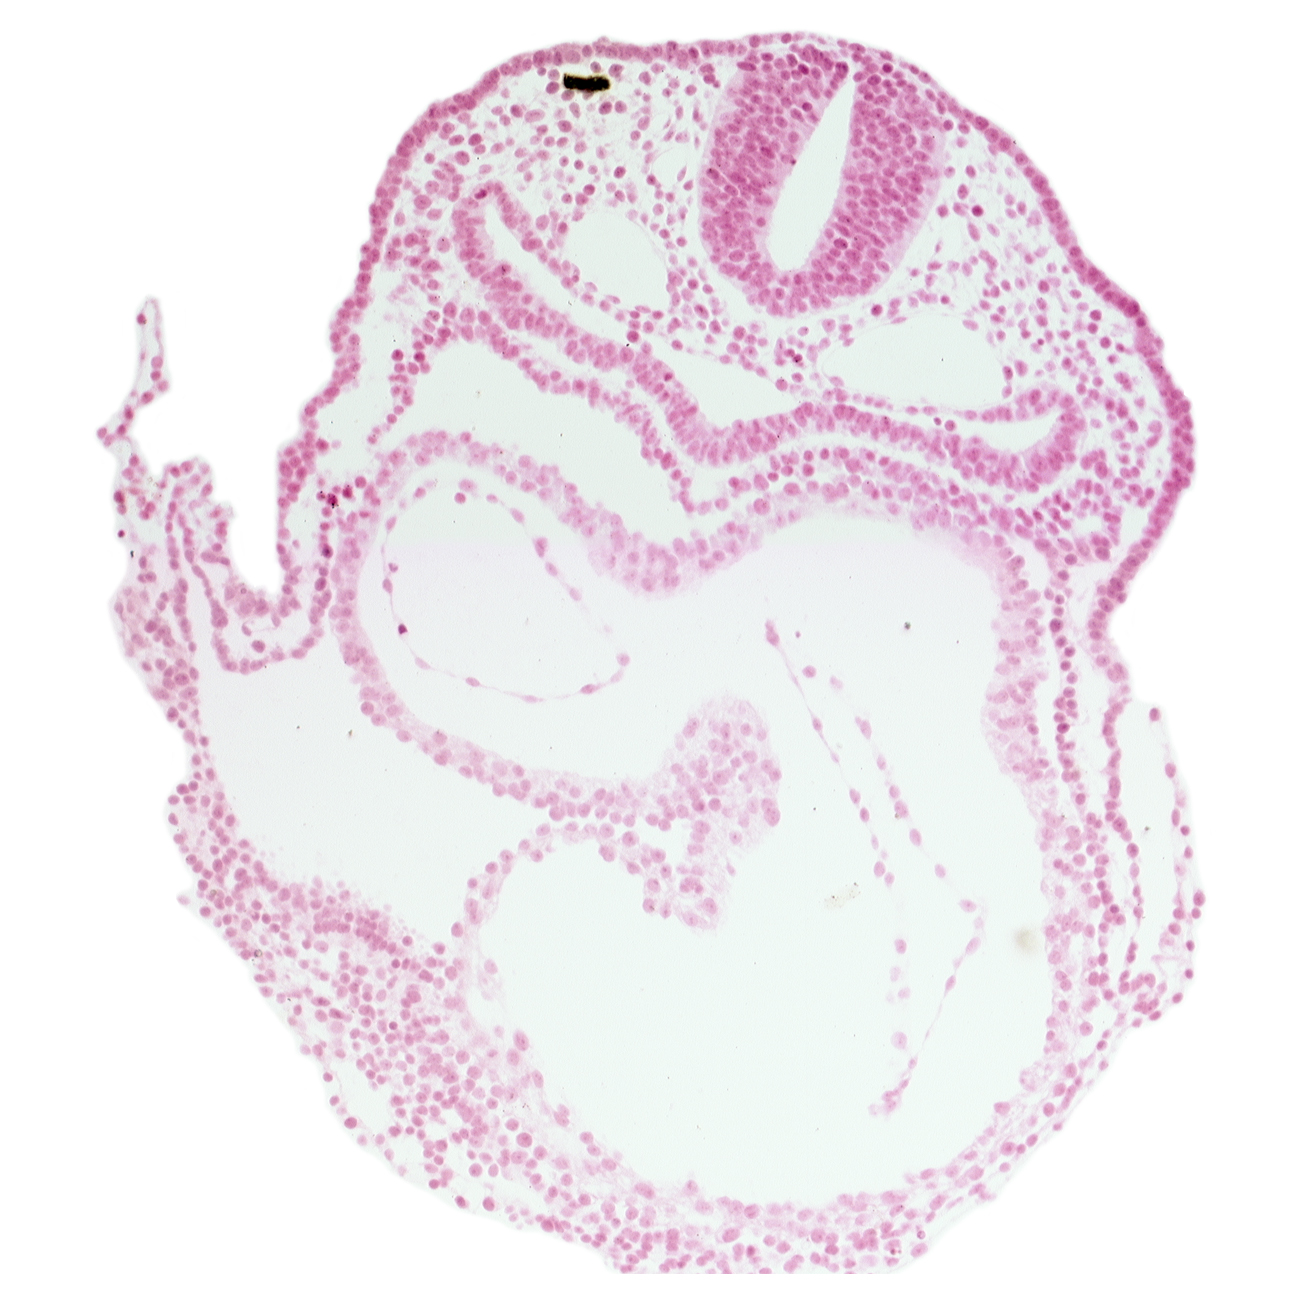

Carnegie Embryo #6344   |   Location: 03-05-04

Keywords: atrioventricular canal, caudal part of respiratory primordium, left atrium, left ventricle, rhombencephalon (Rh. 7), right atrium, vagal neural crest (CN X)

Source: The Virtual Human Embryo.